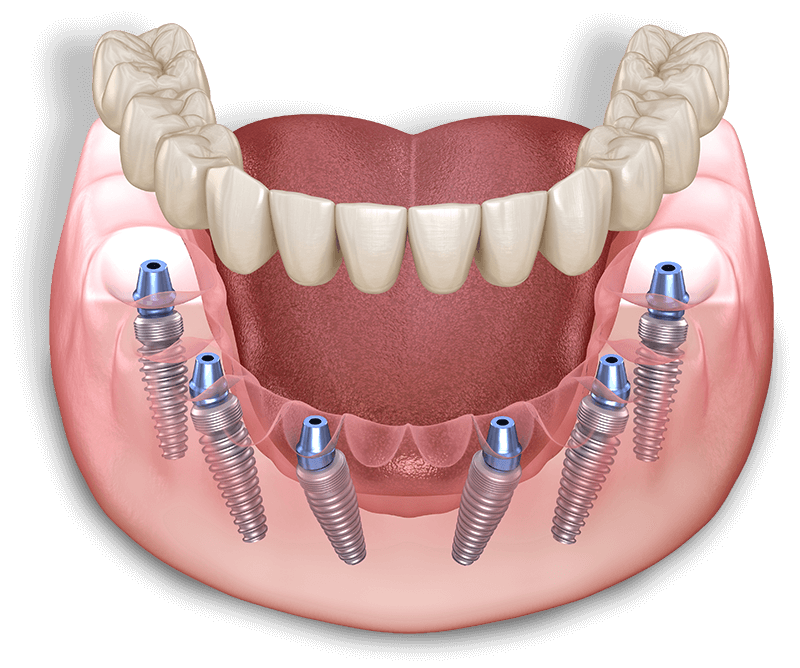

Full Fixed

Set of Teeth

A full, fixed set of teeth offers a permanent solution using the latest dental technology to give you a beautiful smile that’s as good as or even better than the one nature gave you. This option is chip and stain-resistant, doesn’t need to be removed, and is custom-designed to fit securely onto 4-6 implants per arch.